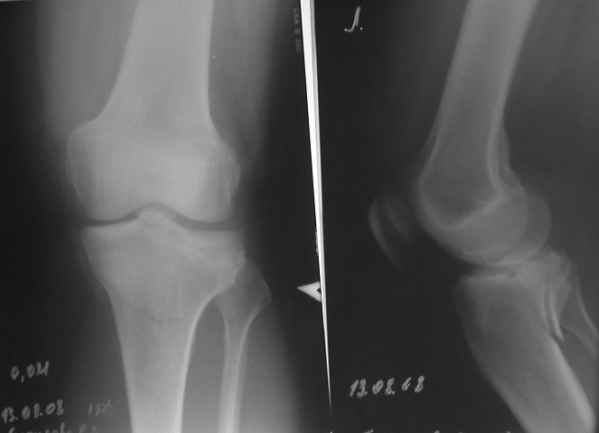

Re: подбор имплантата

конечно есть, просто не дошли. Посылаю